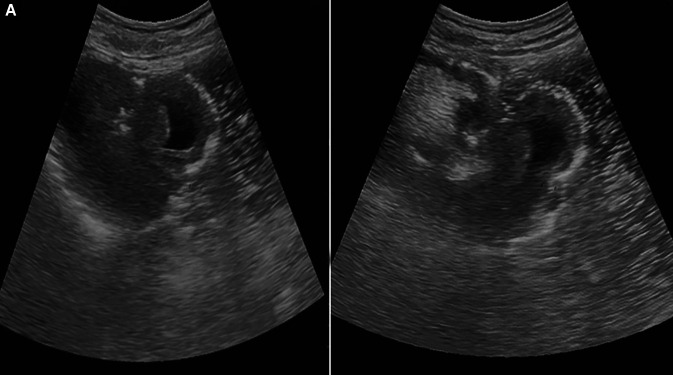

Jejunogastric intussusception (JGI) is a rare, potentially fatal complication of gastrojejunostomy following any gastric resection or gastric bypass surgery. Very less no of cases have been reported to date in the literature, with a very low incidence of <0.1%. Early recognition of JGI followed by prompt intervention is necessary to avoid any serious complications of gut gangrene or even possible death. It carries a mortality rate of approx. 10% of patients subjected to early intervention within 24 hours as compared to 50% in cases where surgery was delayed for more than 48 hours. The usual presenting complaints include a triad of palpable epigastric mass, hematemesis, and epigastric pain with only 50% of patients having this classical presentation. We here, report a middle-aged male with JGI which was diagnosed and managed at our center with emergency surgical intervention.